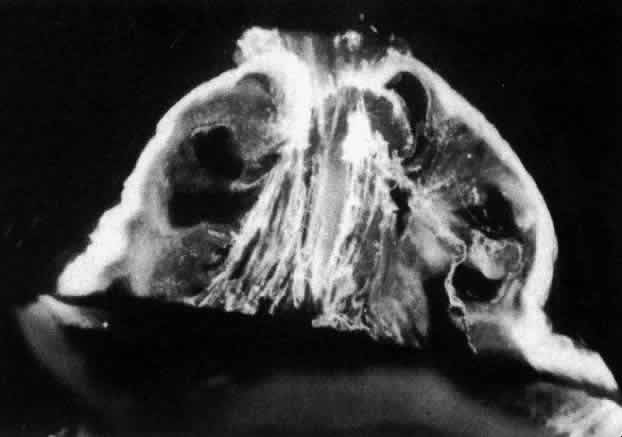

Dissection of the outer layers of the eye (sclera, choroid, and retina) can be performed and the “naked” vitreous body can be maintained intact and attached to the anterior segment of the eye (Fig. 2). This enables study of internal vitreous morphology without a loss of intraocular orientation. However, depending on the age of the subject and consequently the degree of vitreous liquefaction,87 the dissected vitreous will remain solid and intact (young individuals, see Fig. 2) or will be flaccid and collapse. The latter is most often the case in specimens from older adults, and consequently vitreous turgescence must be maintained so as to avoid distortion of intravitreal morphology. Immersion of a dissected vitreous specimen that is still attached to the anterior segment into a physiologic solution maintains vitreous turgescence and avoids structural distortion.

Fig. 2. Human vitreous dissection. A. Vitreous obtained at autopsy from a 9-month-old child. The sclera, choroid, and retina were dissected off the vitreous, which remains attached to the anterior segment. A band of gray tissue can be seen posterior to the ora serrata. This is neural retina that was firmly adherent to the vitreous base and could not be dissected. Because of the young age of the donor, the corpus vitreous is almost entirely gel. Thus, it is solid and maintains its shape, although situated on a surgical towel exposed to room air. (Sebag J: The Vitreous--Structure, Function and Pathobiology. New York, Springer-Verlag, 1989) B. Human vitreous with the sclera, choroid, and retina dissected away; the corpus vitreous is still attached to the anterior segment. The specimen is mounted on a Lucite frame using sutures through the limbus and then immersed in a Lucite chamber containing an isotonic, physiologic solution. This maintains vitreous turgescence and avoids collapse and artifactual distortion of vitreous structure. (Sebag J, Balazs EA: Pathogenesis of cystoid macular edema: An anatomic consideration of vitreoretinal adhesions. Survey Ophthalmol 28[suppl]:493, 1984)